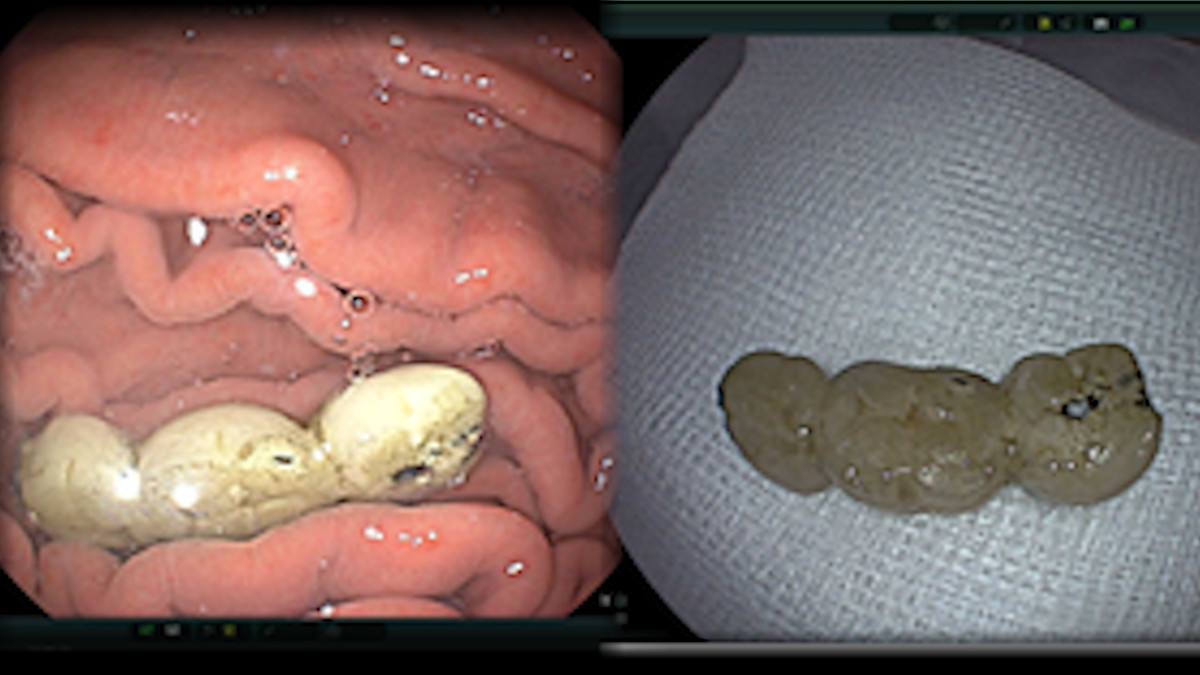

Trường hợp thứ hai là bệnh nhân nam 69 tuổi, đến khám bệnh vì nuốt cầu răng giả bị rơi ra trong quá trình ăn uống. Người bệnh đã được tiến hành nội soi phát hiện dị vật là cầu răng giả dài 4cm nằm trong dạ dày và nhanh chóng gắp ra ngoài an toàn.

Cầu răng giả được lấy ra từ dạ dày bệnh nhân - Ảnh: Bệnh viện cung cấp